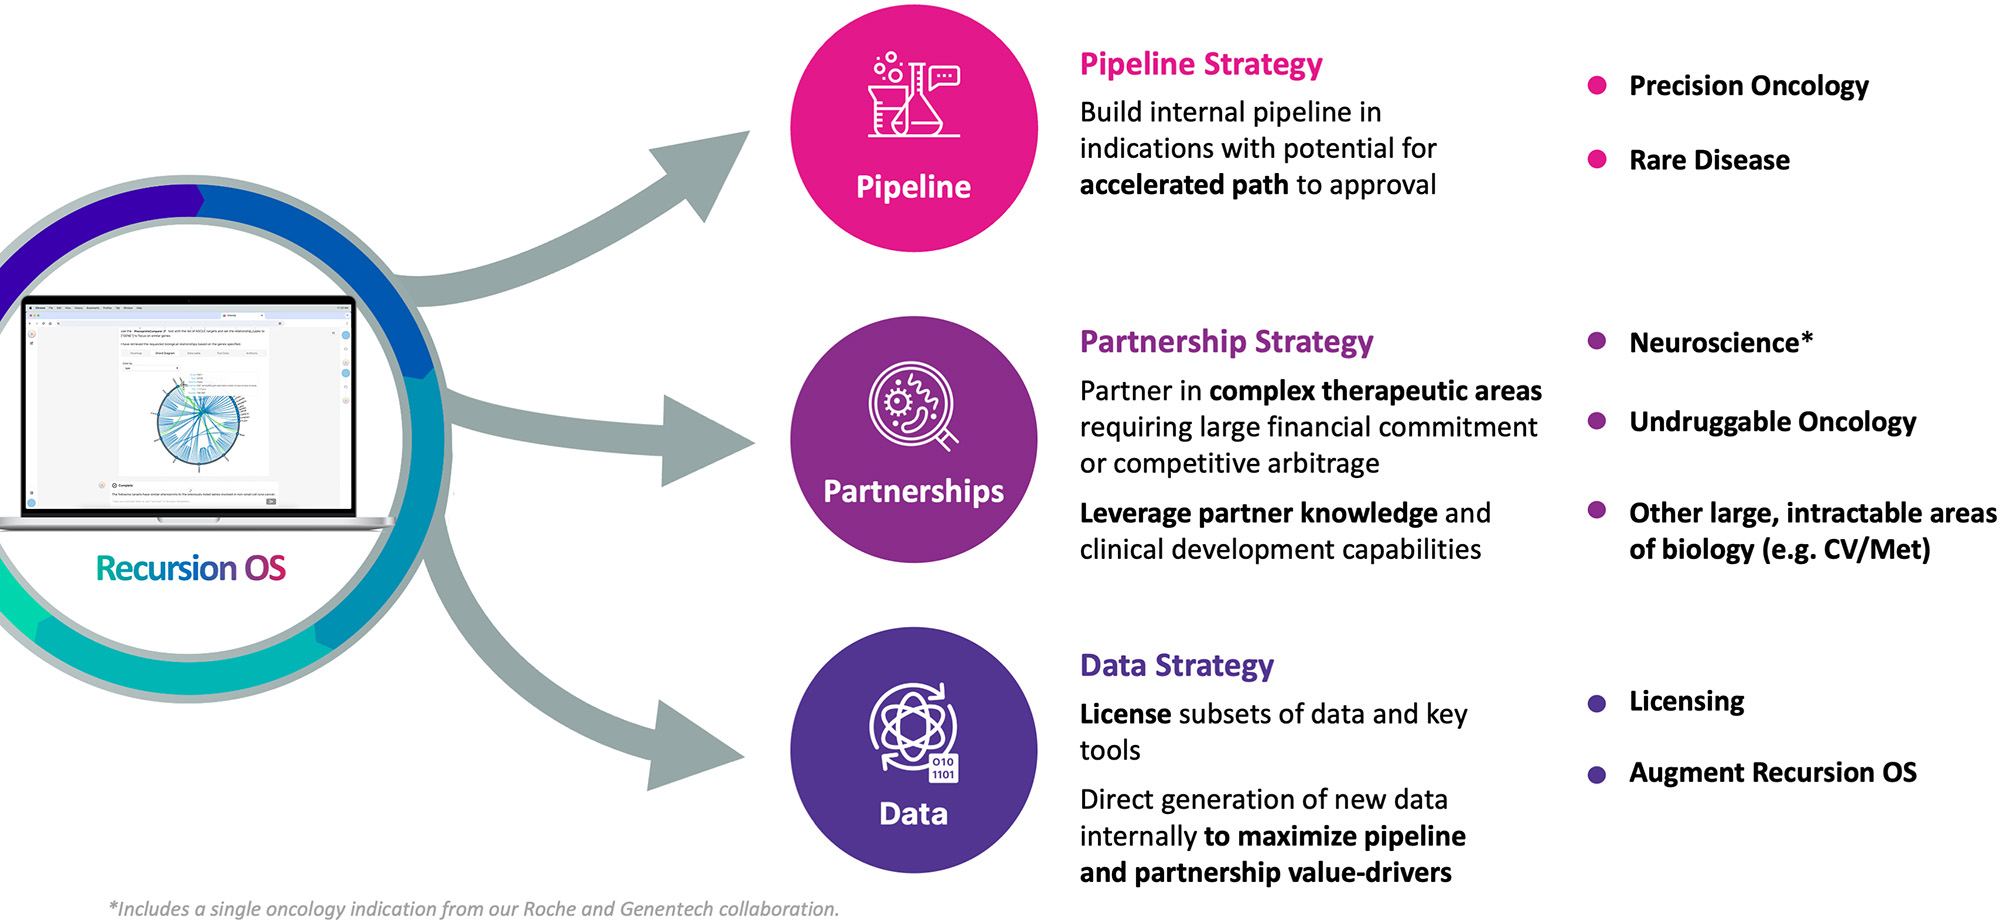

There are three key value-drivers at Recursion:

•An expansive pipeline of internally developed clinical and preclinical programs focused on precision oncology and genetically driven rare diseases with significant unmet need and market opportunities that could potentially exceed $1 billion in annual sales in some cases

•Transformational partnerships with leading biopharma and technology companies to map and navigate intractable areas of biology, identify novel targets, and develop potential new medicines by using advanced computational and data resources

•An industry-leading dataset intentionally designed to capitalize on computational tools and accelerate value created through our pipeline, partnerships and technology products